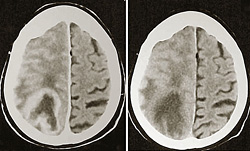

Американцы успешно завершили второй этап испытаний вакцины, способной замедлить рост опаснейшей опухоли мозга — мультиформной слонглиобластомы. До сих пор больные не жили с ней больше года. Лечить ее хирургически почти невозможно: она состоит из бесчисленного множества мелких клеток, рассыпанных по самым разным местам.

Однако медики нашли у глиобластомы ахиллесову пяту. На мембранах ее клеток есть белок EGFRvIII. В здоровых клетках этого белка нет. Значит, можно заставить иммунную систему больного напасть на клетки опухоли, не рискуя повредить здоровые ткани. Что и попытались сделать разработчики вакцины. Испытания прошли в Центре по изучению рака при Техасском университете и в Медицинском центре Университета Дюка. 19 из 23 пациентов пока живы. Некоторые пациенты получают вакцину уже более двух лет.

Попытки подключить иммунную систему организма к борьбе с опухолями головного мозга предпринимались уже не раз. Нынешняя — при всех издержках — стала одной из самых удачных.